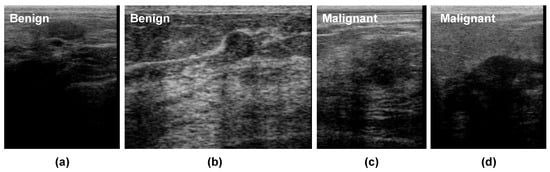

Furthermore, we also computed the malignancy score of each BUS sequence and overlaid it on the BUS images as shown in Figure 8.

Figure 8. Examples of classification results using our method: (top) benign and (bottom) malignant breast masses.

Figure 8 shows the malignancy scores of two BUS sequences having benign tumors (first row) and two BUS sequences having malignant tumors (second row). It should be noted that the malignancy score ranges from 0 to 1, where a malignancy score of 0 stands for no malignancy (i.e., benign tumors). As the malignancy score value approaches 1, the malignancy of the tumor increases. The proposed method obtains very low malignancy scores of 0.023 and 0.0651 for the two benign tumors. In turn, the proposed method produces high malignancy scores for the two malignant tumors.